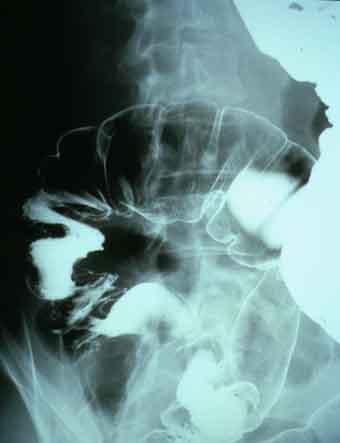

Colitis Hemorrágica debido a E.coli O-157 enteropatógena (Ciudad de Fukuoka, Minami-ku, Takamiya Geka

[Image-ID:636]

Enfermedad Inflamatoria - Ulcerativa/Colitis de tipo patógena

colon/lesión que abarca dos o más regiones del colon

Rayos X